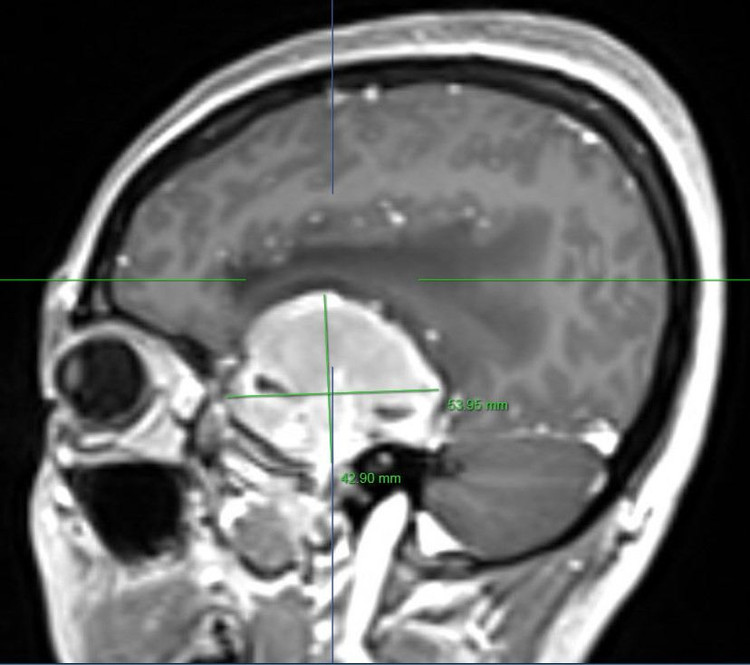

Sau khi được thực hiện các xét nghiệm lâm sàng cần thiết, chụp cộng hưởng từ kết quả cho thấy người bệnh có một khối u màng não vùng hố thái dương trái với kích thước rất lớn khoảng 50mm x 70mm.

| Hình ảnh khối u màng não của bệnh nhân trên phim chụp |

Hình ảnh: Chụp cộng hưởng từ sọ não của người bệnh phát hiện khối u khổng lồ